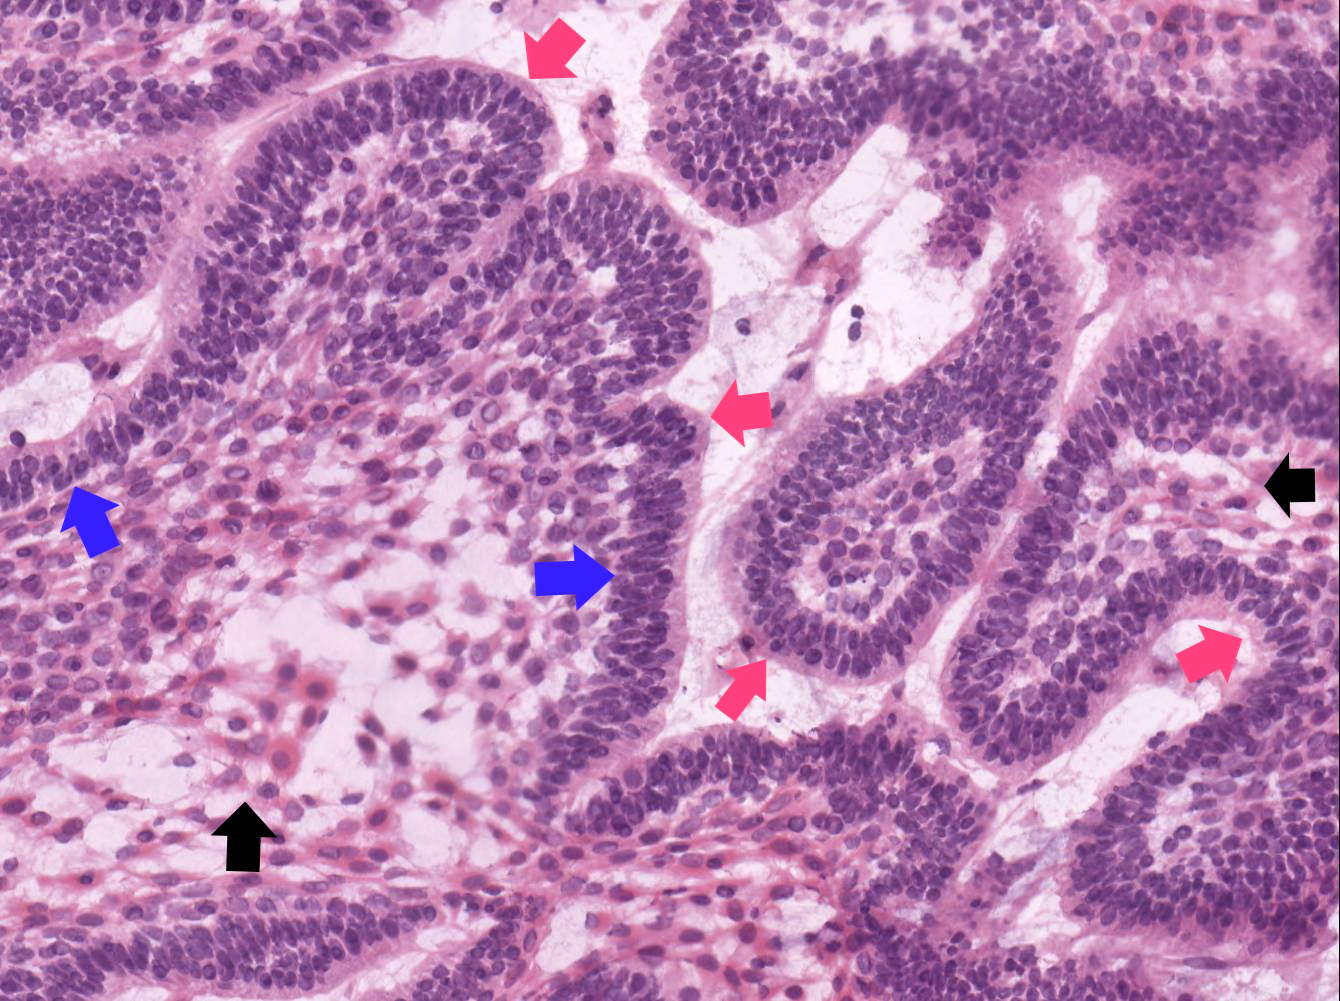

- Within the epithelial islands and cords of conventional ameloblastoma and the cystic epithelial lining of unicystic ameloblastoma, the odontogenic epithelium shows similar changes:

- Columnar cells with hyperchromatic nuclei at basal layer, exhibiting peripheral palisading

- Cells show reverse polarization away from basement membrane (Vickers-Gorlin change)

- Subnuclear vacuolization

- Suprabasal cells with a loose, network-like arrangement, recapitulating stellate reticulum formation seen in normal odontogenesis

- Follicular: most common subtype; islands of odontogenic epithelium in fibrous connective tissue; may be cystic; classic peripheral palisading and stellate reticulum-like areas

- Plexiform: cords and sheets of anastomosing odontogenic epithelial cells; classic peripheral palisading and reverse polarity not always obvious

- Acanthomatous: squamous metaplasia and variable keratinization of stellate reticulum-like cells

- Granular cell: stellate reticulum-like cells have granular eosinophilic cytoplasm; less commonly involves cells at periphery of nests

- Basal cell / basaloid: least common histologic subtype; islands of hyperchromatic basal cells without stellate reticulum-like areas

- Desmoplastic: compressed and angular islands of epithelial tumor cells with dense moderately cellular fibrous connective tissue or collagenous stroma; the formation of metaplastic bone trabeculae is also described

Contributed by Kelly Magliocca, D.D.S., M.P.H. and Anne C. McLean-Holden, D.M.D., M.S.